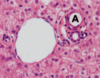

Classical liver lobule - classical liver lobule (outlined by arrowheads) is defined by the arrangement of connective tissue in the portal tract (B) areas and has its centre at the central vein (A) or terminal hepatic venule. Hepatocytes radiate along blood sinusoids from the tracts to the central vein and bile flows in the opposite direction